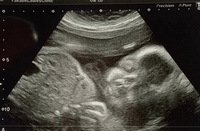

妊娠30週です 赤ちゃんのエコー写真を見て 口唇裂じゃないかとふと不安 Yahoo 知恵袋

妊娠30週 赤ちゃんのエコー写真 超音波写真まとめ たまひよ